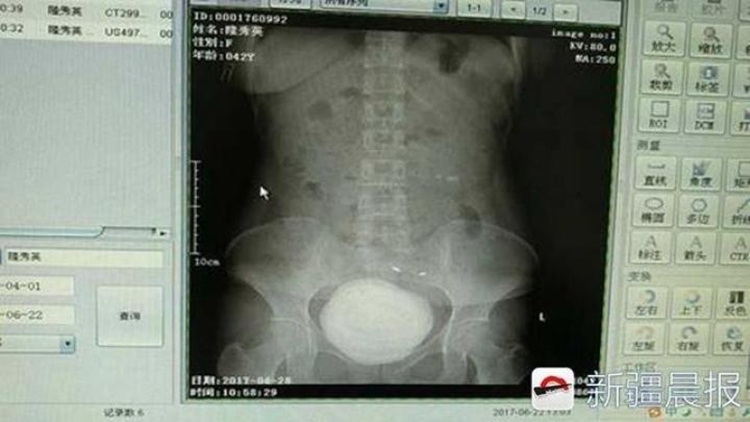

[??? ???? 7? 25?] ?? ??(新疆, ??) ???(阿克蘇, ???)? ?1?????? ?? ?? 1?? ????. ??? ?? ??? ???? ?? 10cm(760g)?? ??? ????? ???. ?? ??? ??? ??? ??? ??? ??? ?? ??? ???? ??.

?? ?? ??? ?? ? ?? “?? ??? ?? ??? ?? ?????. ?? ???? ?? ??? ???? ????? ????? ????. ??? ???? ?? ??? ??????”?? ???. ? ?? ?? ??? ??? ???? ?? ?? ????? ???? ??? ?? ??? ??? ?? ???? ??. ?? ??? ???? ???? ?? ???? ?? ??? ???? ??? ?? ????? ???? ??.

??? ??? ???? ?1?????? ???? ???? ?? ??? ??? ?? ??? ? ?? ??? ??? ????? ?? ?? ?? ???? ??. (??: ???)